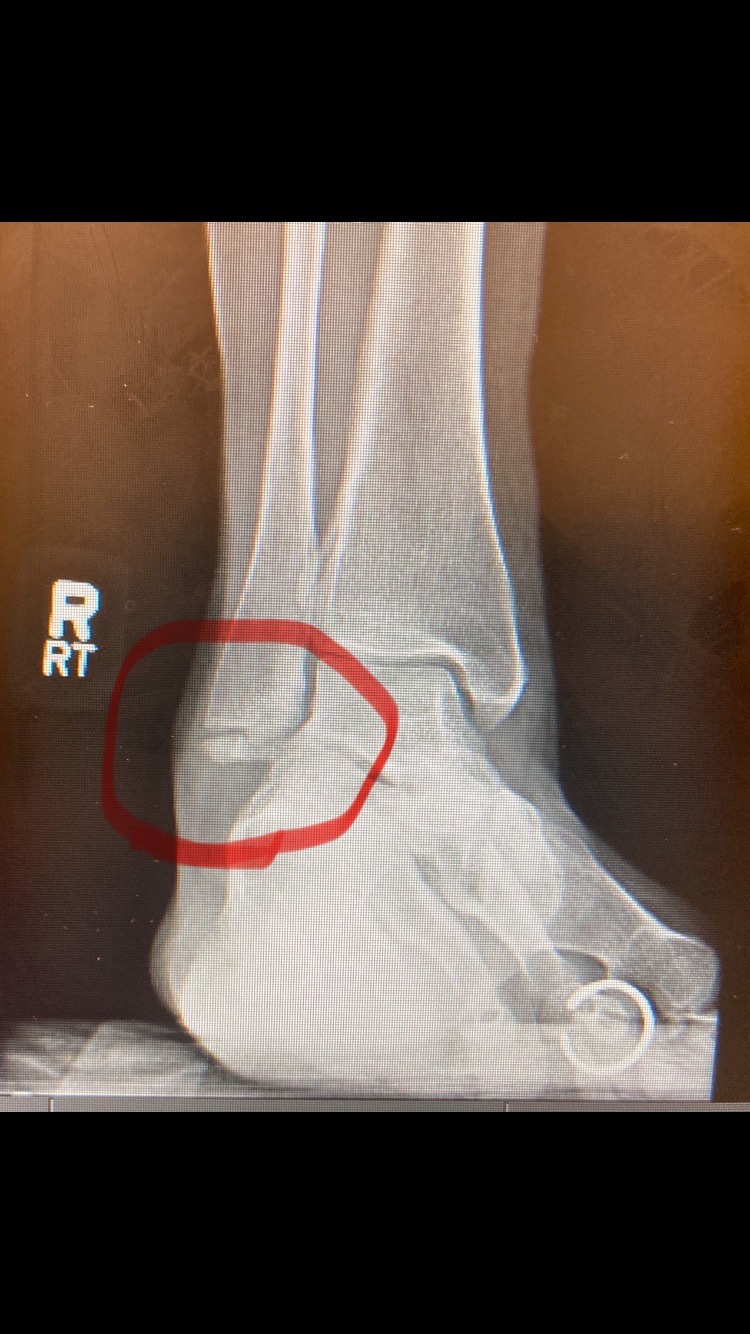

Hi, my name is Jess. I’ve been a veterinary technician for 21 years up until recently when I could no longer perform at my best ability due to breaking my ankle back in April of 2024. Still, I push my body day in and day out, literally walking about on a broken ankle. After a year of not an ounce of healing, my doctor decided to do surgery then. Needless to say, I haven’t been able to work. I’ve fallen into a deep depression because my job was my life, the animals my purpose, and now it’s gone. I have 80 cents to my name, so I can’t pay the bills. I’m filing for disability, which can take a while, which is why I’m asking for help. Even the smallest donation will make a huge difference.